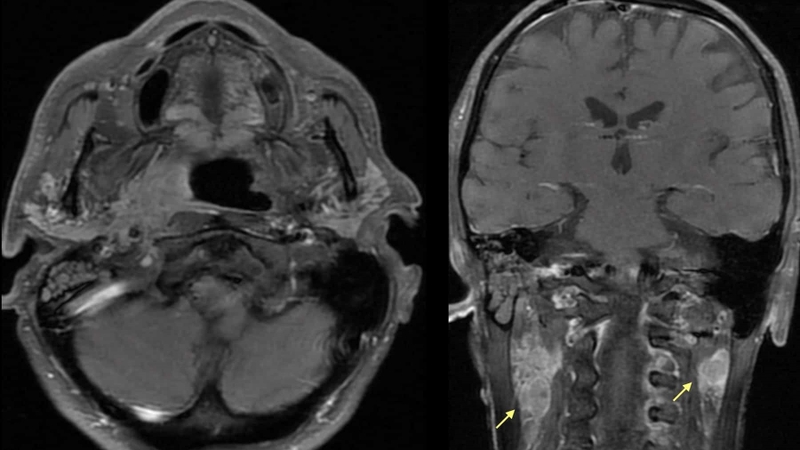

Phim X-quang thường quy không cho thấy dấu hiệu đặc trưng, nhưng cộng hưởng từ (MRI) lại có thể cung cấp hình ảnh rõ ràng về khối nang, với đặc điểm giảm âm, giảm tỷ trọng và ranh giới rõ rệt. Nhờ đó, kích thước và vị trí của nang sẽ được xác định một cách chính xác.